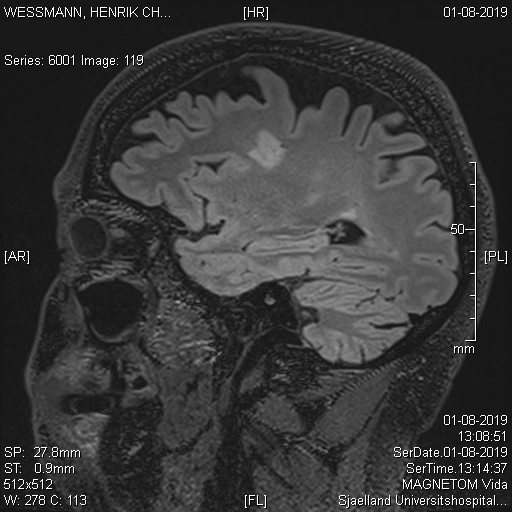

Med en MS diagnose har heg også tydelige kognitive tab og nu fik jeg det sort på hvidt.

Det gjorde mig ked af sådan at blive konfronteret med nogle effekter af 14 år med sclerose